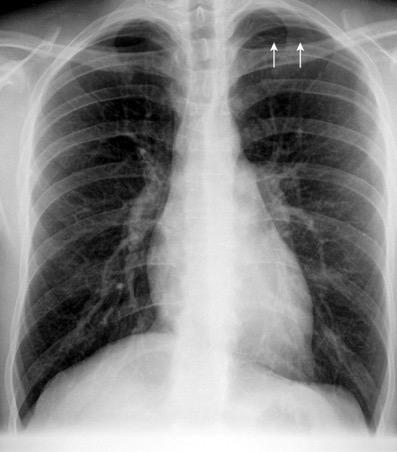

91. NEUMOTÓRAX EN ESPIRACIÓN

M. Bradley et al. Value of routine expiratory chest films in the diagnosis of pneumothorax.Arch Emerg Med.1991, F. Schramel, et al. Expiratory chest radiographs do not improve visibility of small apical pneumothoraces by enhanced contrast.Eur Respir J. 1996,

Sospecha de neumotórax Neumotórax